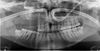

This 22-year-old patient underwent a posterior right maxillary resection extended to the orbital floor (Brown III-b class) due to a malignant peripheral nerve sheath tumor (MPNST). Teeth 14 to 17 were sacrificed during surgery (Figs. 2 and 3). Primary reconstruction was performed using a free radial forearm flap, thereby avoiding the need for a vascularized bone graft. Two ZI were placed in positions 14 and 17, along with a CI in position 15, following ramus bone grafting (Fig. 4). The resulting tripod configuration allowed for the stable fixation of the prosthesis and immediate functional loading. At four years of follow-up, both ZI and CI show a 100% survival rate, with a fully functional prosthesis and an uneventful postoperative course.

Fig. 3 Postoperative panoramic radiograph showing the post-surgical defect classified as a Brown III-b class. |